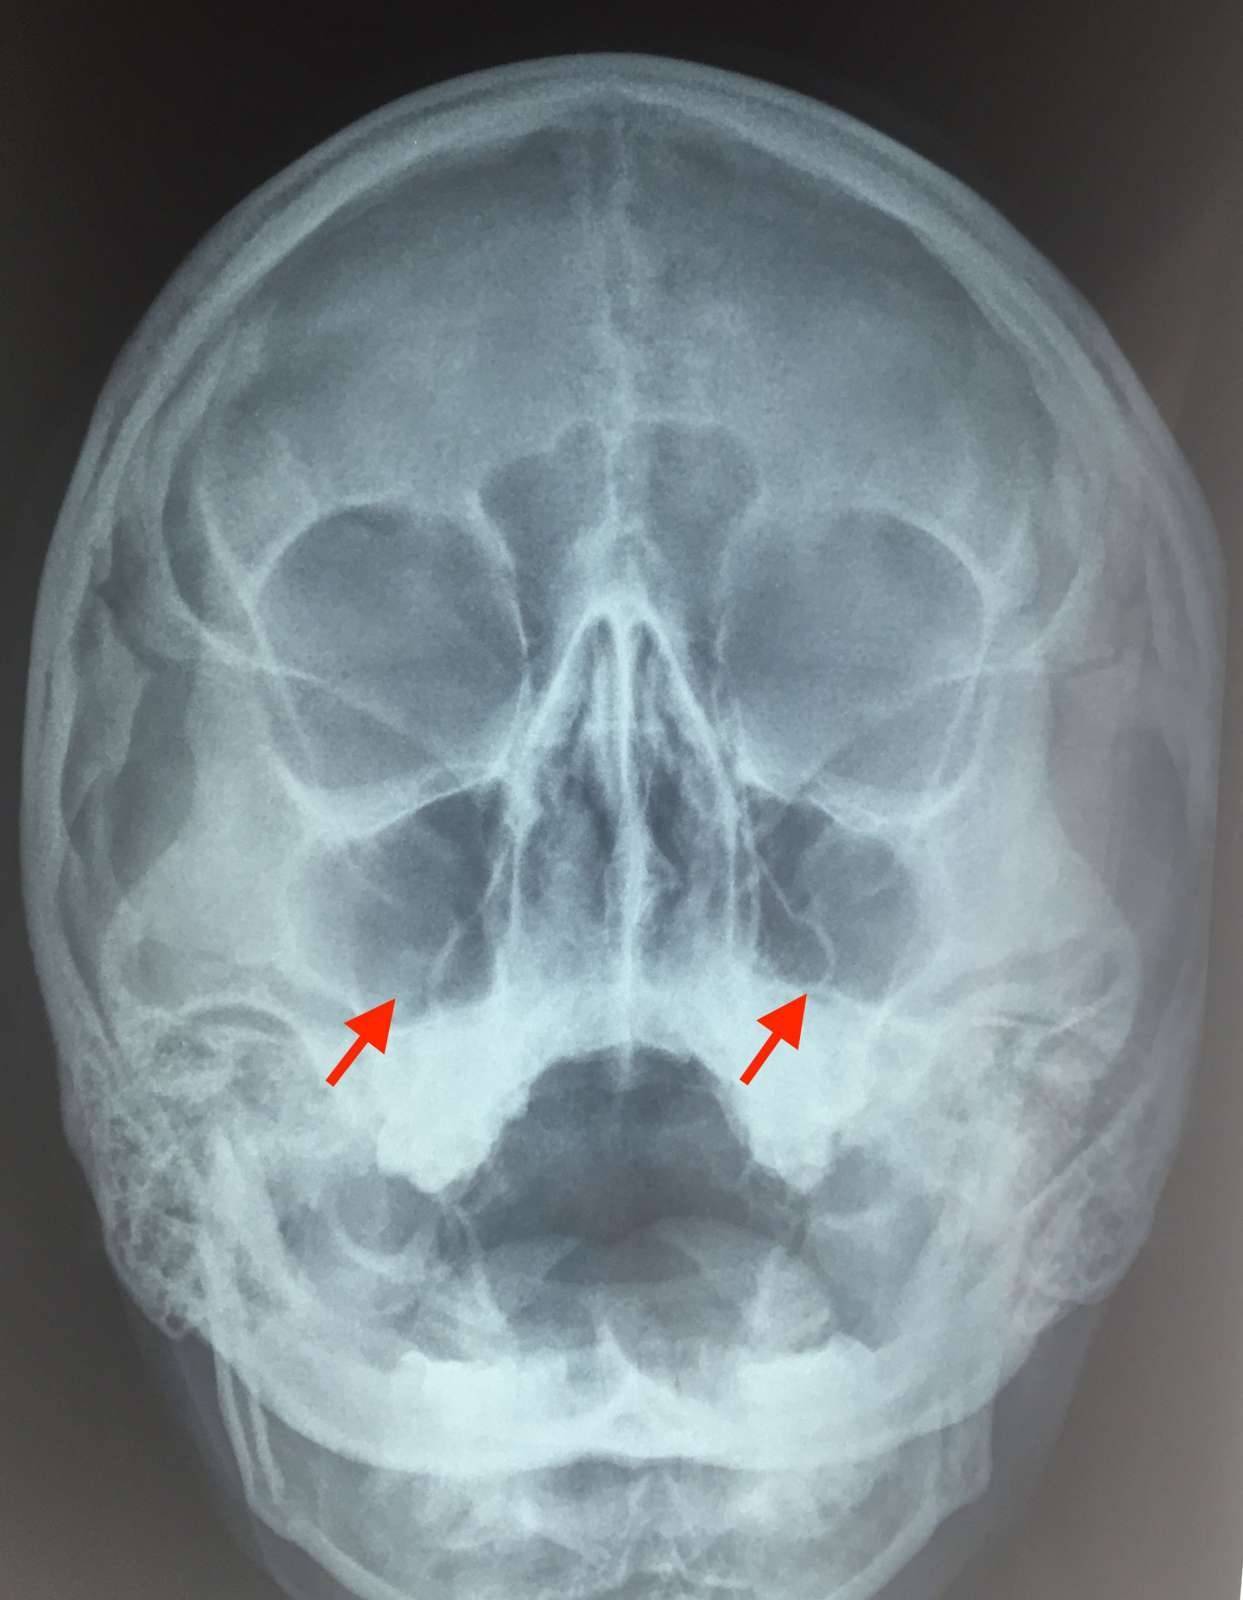

Если судить по месту локализации воспаления, гнойный гайморит бывает односторонним и двусторонним. При двустороннем гайморите воспалены обе пазухи, при одностороннем – либо правая, либо левая. Соответственно, и гайморит будет правосторонним или левосторонним.

Острая форма начинается и развивается стремительно и характеризуется яркими симптомами. Самый узнаваемый признак воспаления гайморовых пазух – сильная боль в переносице и месте локализации пазух – под глазами в области щёк. Гной, находящийся в пазухах, давит на их стенки, что вызывает болевые ощущения. Боль становится сильнее в вечерние часы и при наклоне головы. Иногда она может отдаваться в висках или челюсти.

Другой явный признак заболевания – гнойные выделения из носа зелёного или жёлтого цвета, которые могут иметь неприятный запах. В некоторых случаях наблюдается стойкая заложенность носа, когда соустья пазух перекрыты, и насморк отсутствует, так как гнойные массы не могут выйти наружу. Заложенность носа приводит к появлению гнусавости в голосе и снижению обоняния.